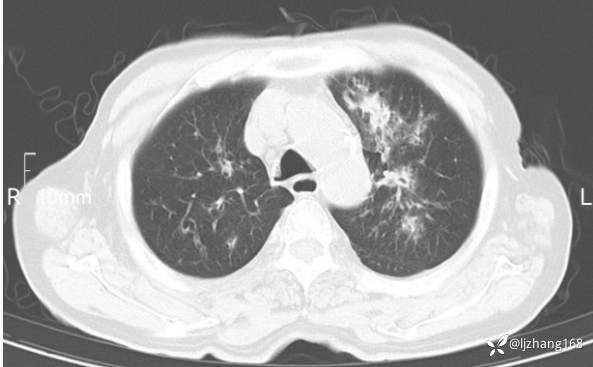

老年男患,咳嗽,气短,双肺多发间质性病变,何种感染?(有结果)

辅助检查:胸部CT:双肺肺气肿,间质性病变,血气分析:PH 7.413, PCO2 29.2mmHg, PO2,81.8mmHg,乳酸 3.3mmol/1,剩余碱-4.0mmol/1,HC03 18.8mmol/1。全血超敏C反应蛋白:超敏C反应蛋白 135.60 mg/L、 白细胞 14x19^9/L,中性粒细胞11.6x10^9/L。